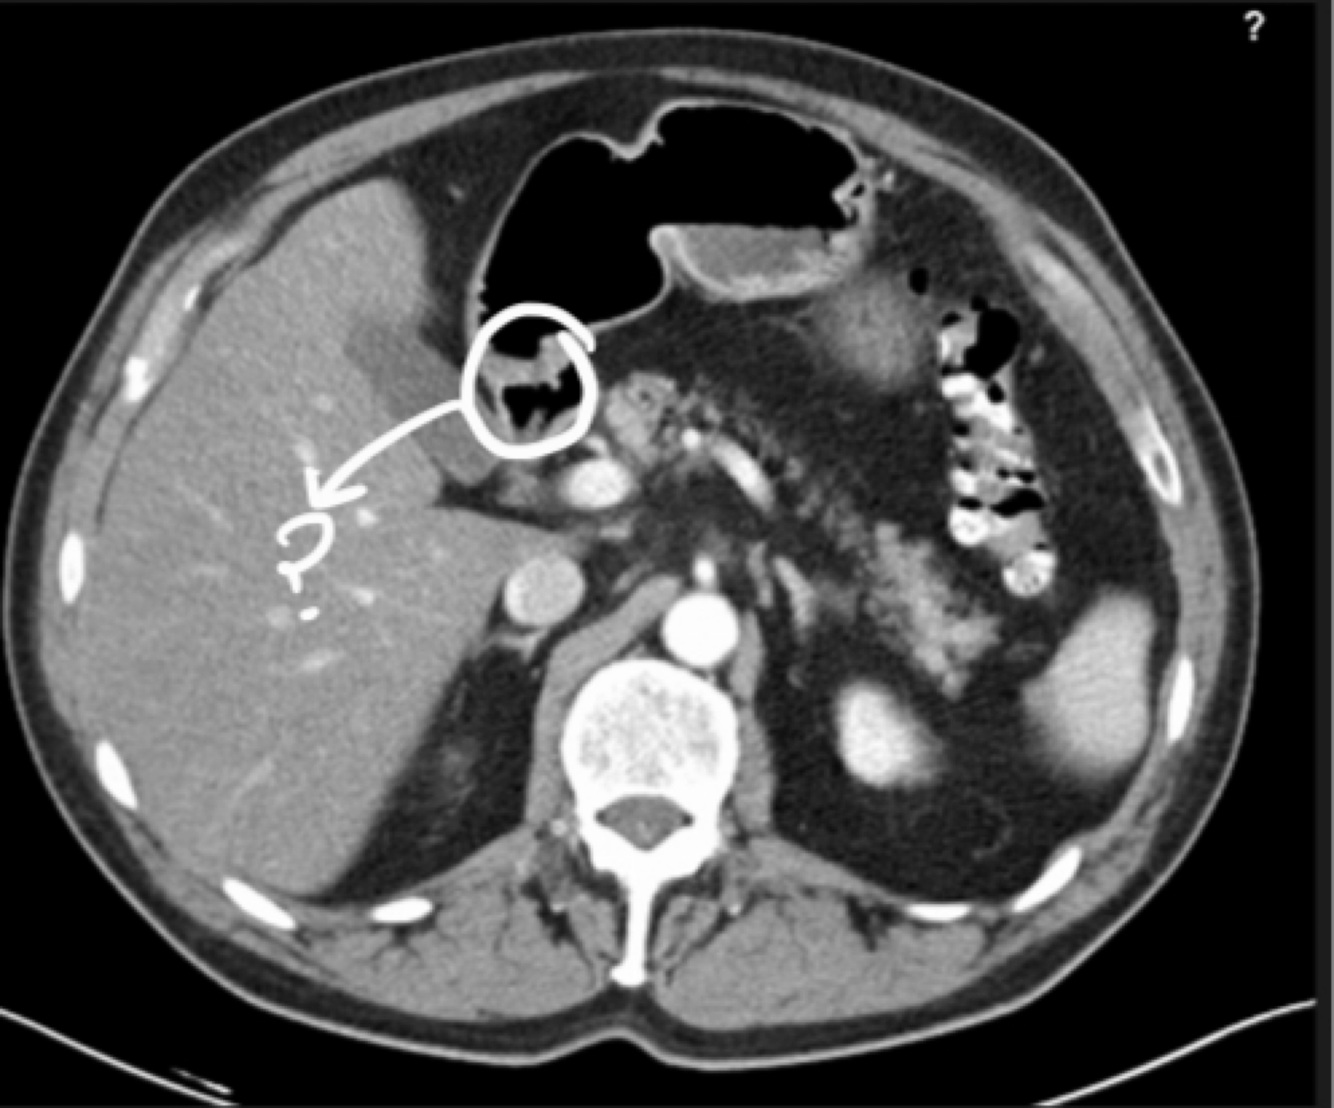

Q

Name the marked structure

A